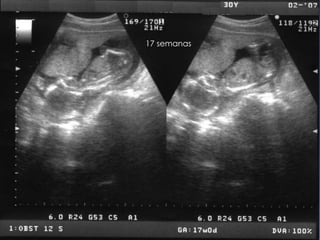

17 semanas